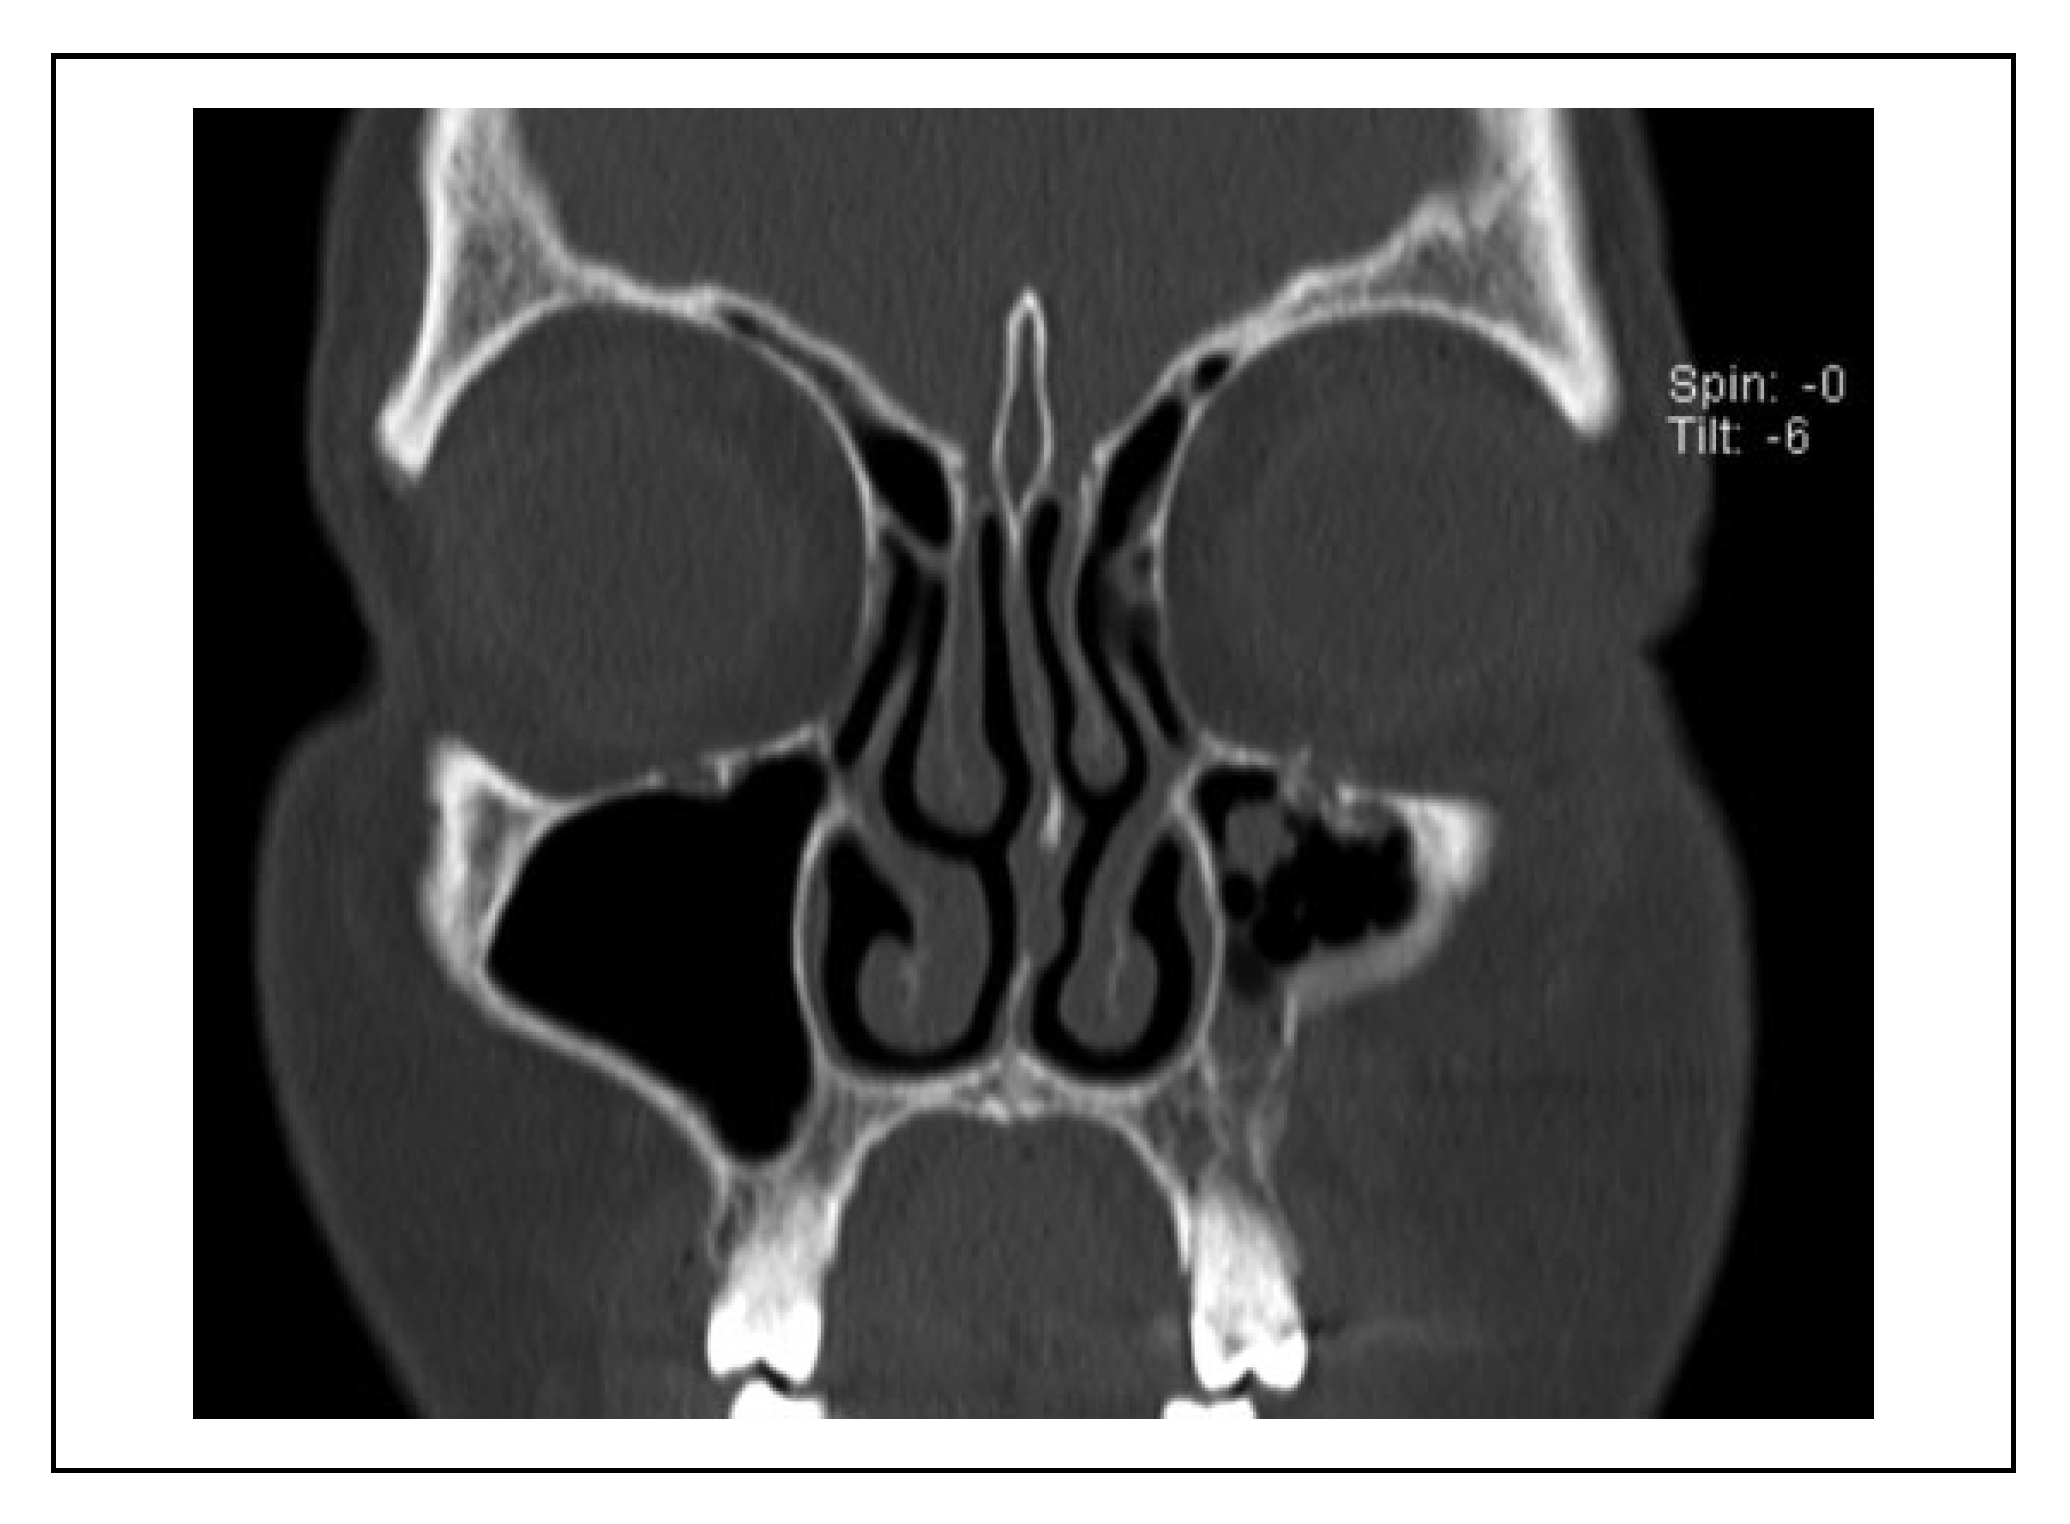

A case was considered to show involvement of the fracture course through the infraorbital canal (IOC) when the fracture line penetrated the cortex of the IOC at one site or more (Figure 2). When the fracture line was near the IOC (within 1 mm), this indicated that the cortex of the IOC was still intact (Figure 3).

Figure 2. Patient with a left zygomaticomaxillary complex fracture with the fracture line through the infraorbital canal and penetration of the cortex of the infraorbital canal. This patient experienced hypoesthesia of the infraorbital nerve.